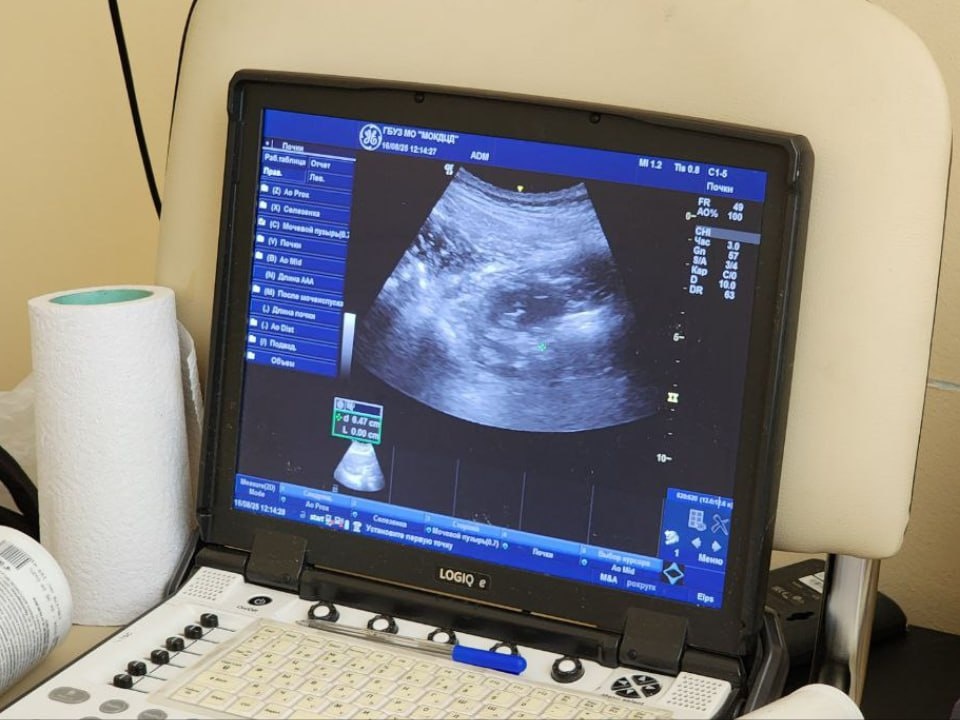

Фото: МедиаБанк Подмосковья/Рой Евгений Александрович